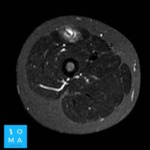

🔹Varón de 12 años que consulta por tumefacción en región anterior de muslo derecho. Refiere molestia a ese nivel 3 días antes, después de pique en partido de fútbol.

🔹Cambios inflamatorios asociado a edema y banda líquida que rodea a la unión miotendinosa central del sector medio del músculo recto anterior del cuádriceps derecho, de 10 mm de extensión, evocador de desgarro de la unión miotendinosa grado II.